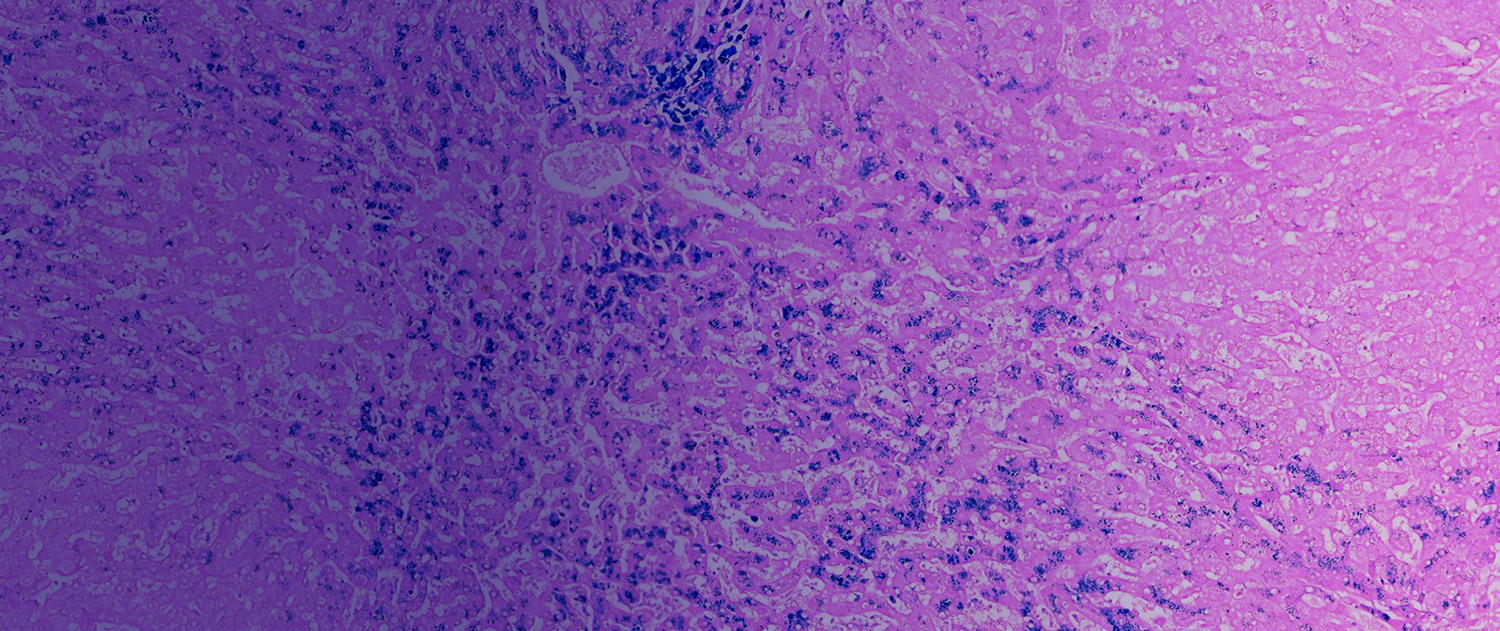

GALERÍA DE IMÁGENES

con espesor ideal. - Aplicar técnica tinción rápida de

Hematoxilina-eosina para visualización tisular. - Identificar y corregir errores